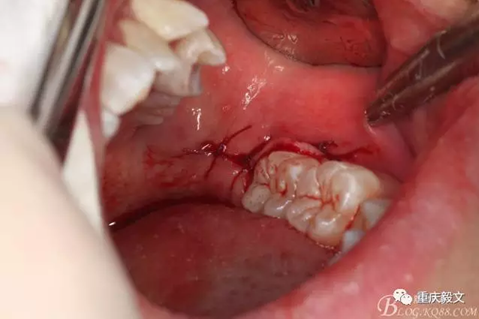

圖10.縫合??p合牙齦切口。檢查無明顯出血,將牙齦切口對位后縫合。原則上不切不縫,若切必縫。即只要切開,就必須縫合。最后咬棉花或紗布止血。醫(yī)囑。必要時,給予抗感染治療